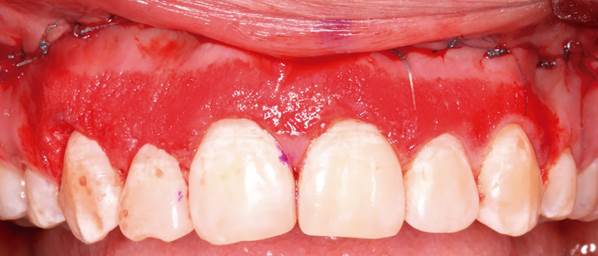

Antes y después del reposicionamiento labial

Los resultados suelen apreciarse desde las primeras semanas tras la intervención. La sonrisa se vuelve más equilibrada, reduciendo la cantidad de encía visible sin modificar la naturalidad facial.